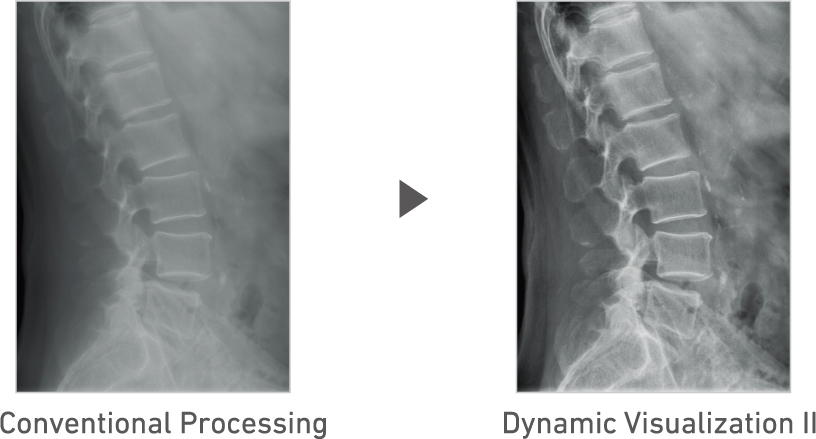

3D structure analysis technology to support mobile exam

Advanced recognition algorithms automatically adjust contrast and density for individual body parts based on calculation of estimated 3D image data.*5